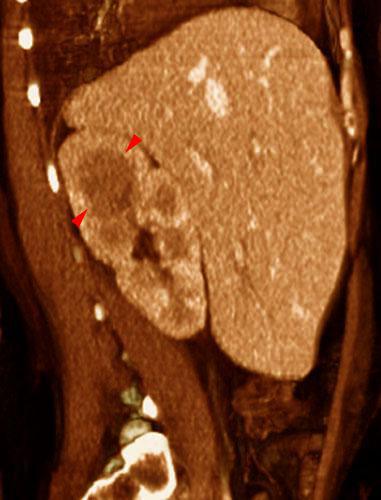

Pielonefritis aguda 1

VR seccional. Visión sagital derecha. Riñón derecho aumentado de tamaño y con disminución de la contrastación. Área hipodensa (puntas de flecha) en su polo superior